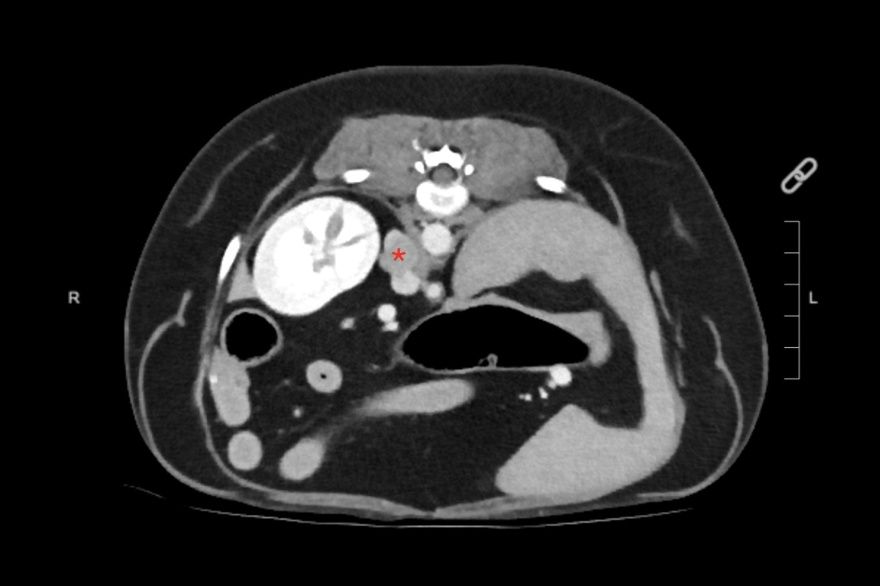

El feocromocitoma es un tumor de la médula suprarrenal que afecta tanto a perros como a humanos. Produce un exceso de hormonas como la epinefrina y la norepinefrina y puede causar complicaciones cardíacas potencialmente mortales.

En la medicina veterinaria, este tumor poco frecuente pero de gran relevancia clínica, suele pasar desapercibido debido a signos clínicos inespecíficos -como hipertensión, colapsos o taquiarritmias- que se confunden con otras afecciones hormonales o cardiovasculares.